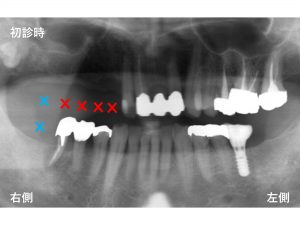

以下が初診時です。

右側の奥歯が欠損しています。

✖︎:青印と✖︎:赤印が欠損している部位です。

上顎の右側奥歯では、5歯が欠損していることになります。

しかし、下顎右側の奥歯も1歯欠損しています。